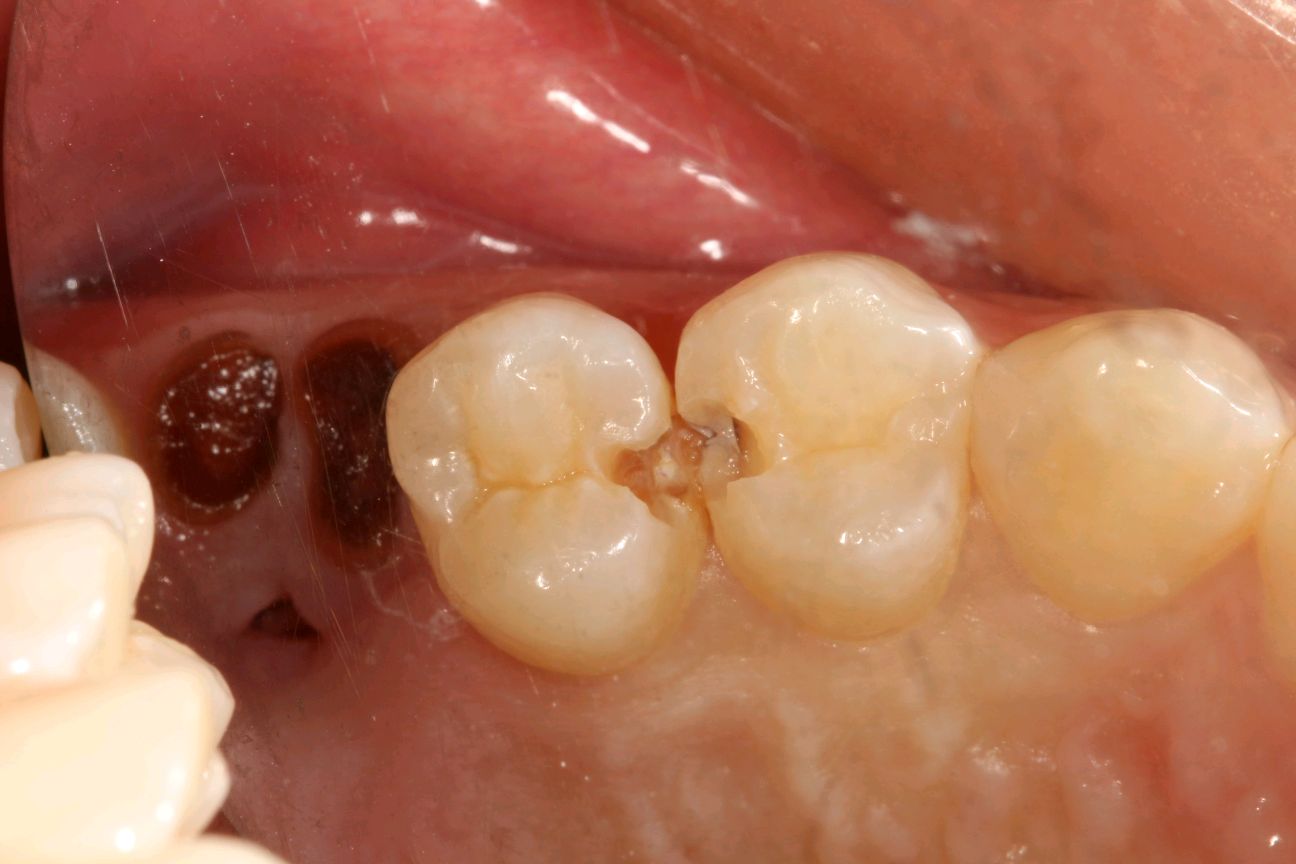

患者女,34岁,24、25邻面龋坏。经患者同意去腐备洞行嵌体修复。后通过德国 CEREC 技术扫描后,数据分析精准有效,"量身定做"专属于自己的修复体。患者当天即可配戴,既保证了边缘的密合性,还确保了色泽和形态的美观。患者不会有很强的异物感和咬合的不适。大大提高了工作的效率,也节省了患者的时间。

术前